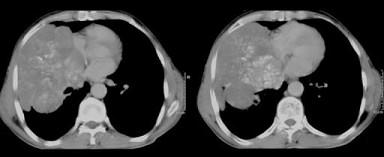

50岁,男性,右侧胸痛、咳嗽、咯血3个月,请结合图像选择最可能的诊断 ( )A、胸膜间皮瘤B、韦格肉芽肿C、肺结核D、肺癌E、纵隔肿瘤

问题 50岁,男性,右侧胸痛、咳嗽、咯血3个月,请结合图像选择最可能的诊断 ( )

选项 A、胸膜间皮瘤 B、韦格肉芽肿 C、肺结核 D、肺癌 E、纵隔肿瘤

答案 D